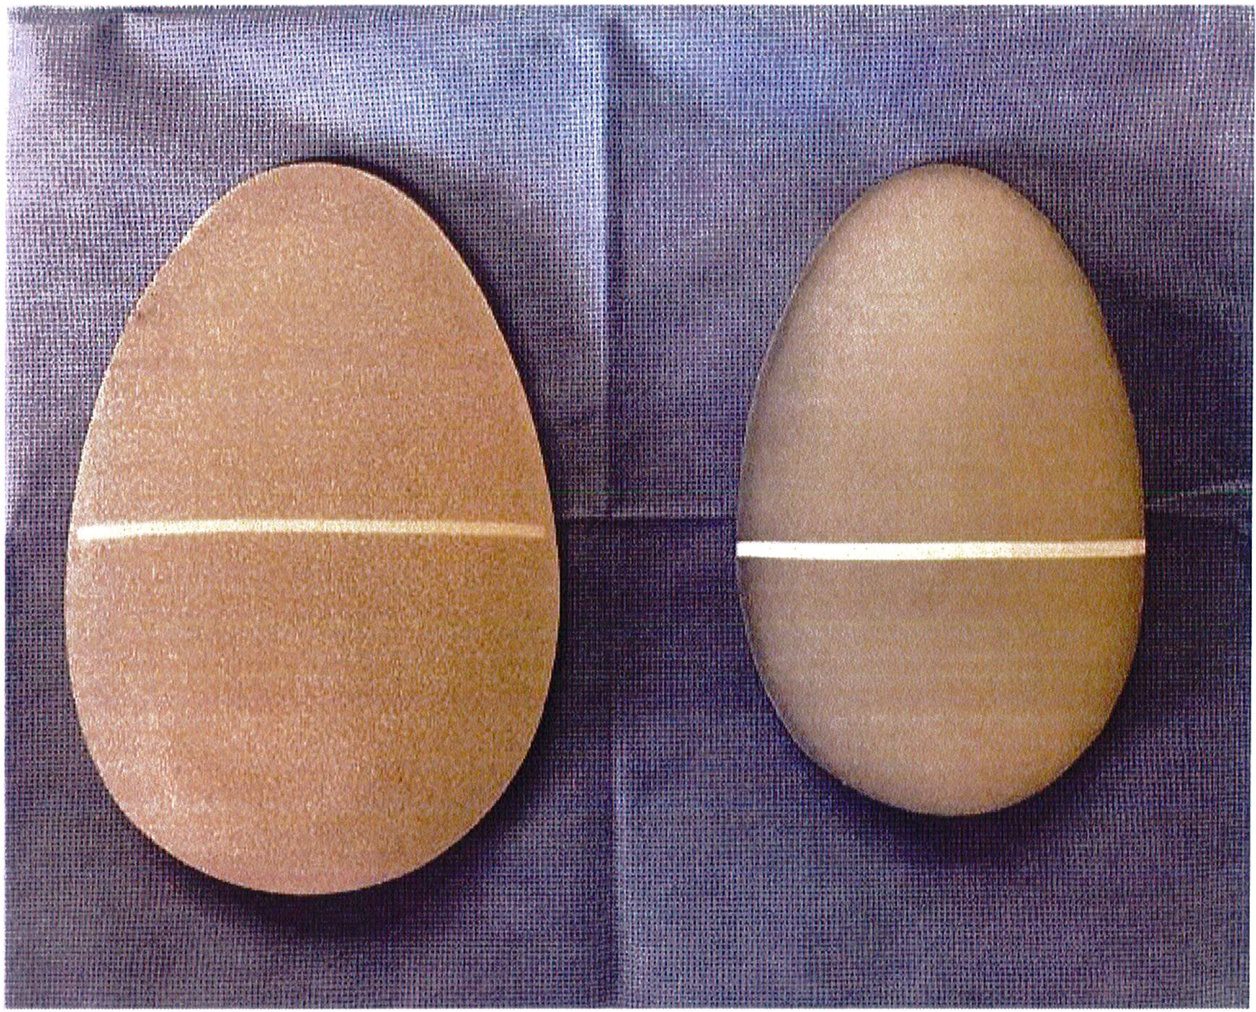

Sau đó, mô cấy sẽ được đưa vào, đảm bảo rằng nó được căn chỉnh hoàn hảo, thẳng trục và vừa khít bên trong túi (Hình 15). Chúng tôi nhấn mạnh rằng tất cả các khối implant đều phải có 1 đường trắng chạy ngang qua tâm điểm của chúng để tạo thuận cho việc căn chỉnh vị trí (Hình 16). Không bao giờ được đặt khối implant chếch vì chúng sẽ tạo ra hiệu ứng bong bóng kép ở ¼ dưới ngoài vùng mông (Hình 17).

Hình. 17. Khối implant silicone (bên trái) và elastomer (bên phải) với một vạch trắng ở giữa để giúp Bác sĩ có thể định vị chúng khi phẫu thuật.